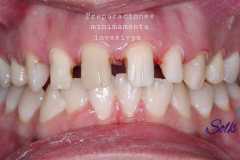

Caso 2

Paciente femenina, 19 años, con agenesia dental (ausencia de piezas de nacimiento), se realiza colocación de 2 implantes en piezas laterales, confección de provisionales y se esperan 4 meses para la colocación de piezas permanentes sobre implantes.